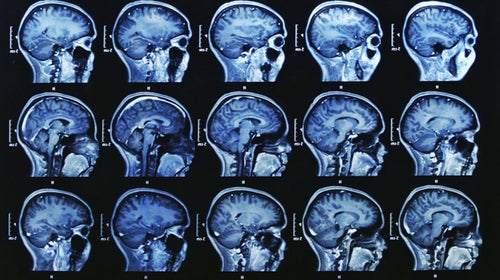

Women's brains may recover faster than men's after a concussion. (Photo: Bunyos/Getty)

Using diffusion tensor imaging (DTI), an advanced form of MRI, researchers studied the imaging results and medical records of 47 male and 22 female patients diagnosed with concussions, also known as mild traumatic brain injury (mTBI). They also studied the results of 22 control participants, 11 women and 10 men.

DTI gives scientists a measure of the movement of water molecules along axons, nerve fibers in white matter that allow communication between various areas of the brain. Healthy brains have a high value of this measurement, called fractional anisotropy (FA); in patients with brain injuries, a low FA is linked to cognitive impairment.聽

Researchers found male patients with concussions had much lower FA levels within a white matter tract that connects the frontal and temporal lobes of the brain, called the uncinate fasciculi (UF). They also found that FA levels in that particular area of the brain were the best predictor of recovery time, better than patient reports of their own symptoms.聽